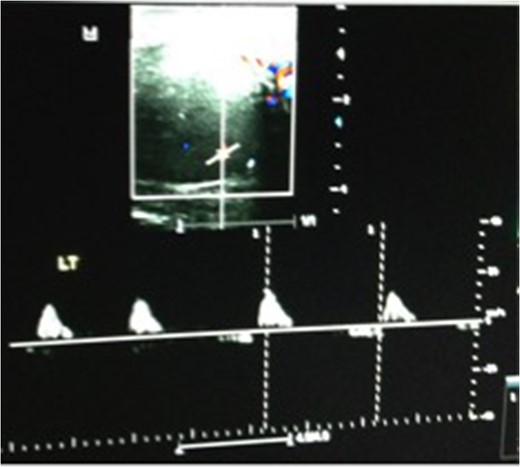

We present a case of a 37-year-old man presented to the Emergency department with a 3-day history of left testicular pain. He had no chronic illnesses and was not immunocompromised. The pain was associated with mild storage lower urinary tract symptoms. He was sexually active but had no previous sexually transmitted diseases and no urethral discharge. He had no history of trauma and had not had any similar episodes before. His examination revealed a swollen tender left testicle; equivocal for testicular torsion. A Doppler ultrasound was done which revealed increased flow to the left testicle with no evidence of testicular torsion (Fig. 1). The patient was subsequently discharged on oral ciprofloxacin, analgesia and instructed to perform scrotal elevation. The patient subsequently presented 6 h later with worsening of his pain and was reviewed and re-imaged with a color Doppler. At this time, imaging findings demonstrated reversal of diastolic flow a feature suggesting impending infarction, along with other features of acute inflammation (Fig. 2). The patient was taken to the operating room and a scrotal exploration was performed. No evidence of torsion was identified. A congested testicle was observed. No evidence of infarction or abscess formation was seen. Day 1 post-operatively the patient continued to have left sided testicular pain, now associated with lower abdominal pain. A KUB ultrasound and a repeat scrotal ultrasound were performed. These demonstrated absent flow in the left testicle (Fig. 3). On repeat exploration a dusky blue testicle was found and a left orchidectomy performed. Testicular histopathological analysis demonstrated features suggestive of acute necrotizing inflammation of the testes and epididymis as well as the spermatic cord and its vessels. Cultures of the urine subsequently showed significant growth of Escherichia coli.

Repeat ultrasound scan 6 h later showing reversal of diastolic flow.